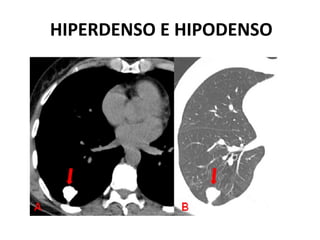

ESCALA HU

HIPERDENSO E HIPODENSO

ISODENSO